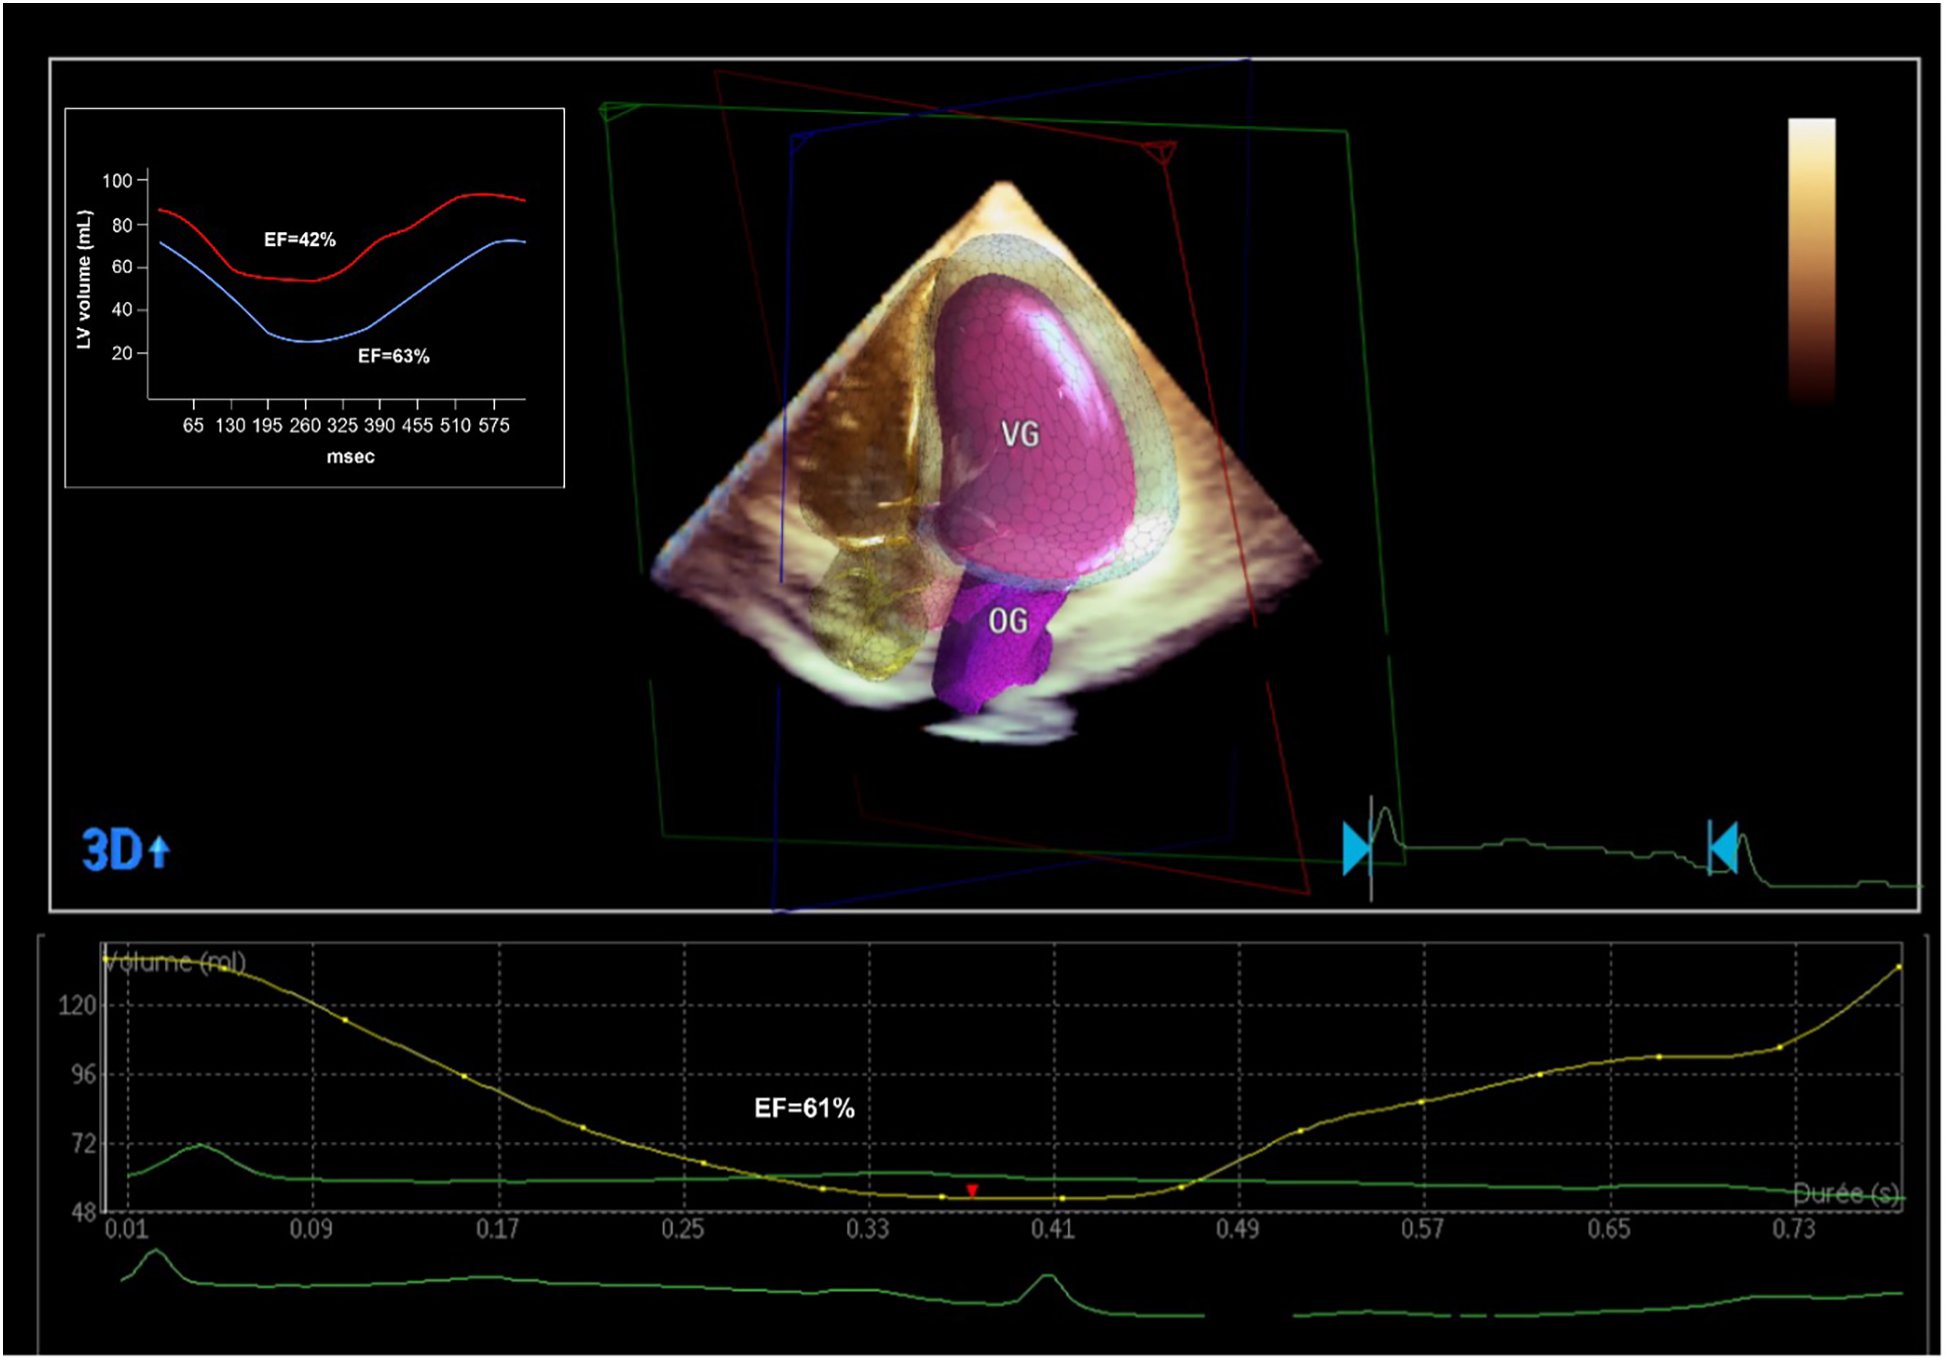

A TTE at day 5 showed complete recovery of the LVEF without any regional abnormalities (Figure 3).

Figure 3

Echocardiographic and PET-CT evaluation of the LVEF after the coronary revascularization. PET-CT showed a significant improvement in LVEF (from 42% to 63%) with a significant decrease globally in LV volumes, denoting an ischemic LV dilatation. 3D echocardiographic evaluation confirmed the normalization of the LVEF.

Myocardial ischemia is a key factor for guiding revascularization strategy in patients with stable coronary artery disease (2). The role of myocardial viability, though, is less clear. Historically, many observational studies and meta-analyses have suggested that in patients with dysfunctional myocardium, revascularization is associated with better outcomes and improved ventricular recovery when myocardial viability has been proven by advanced imaging (3). However, more recent controlled trials (STICH and REVIVED-BCI2) showed no benefit in survival with revascularization compared to optimal medical treatment in patients with decreased LVEF despite preserved myocardial viability (4, 5). These findings do not apply in acute, complex cases where viability may help differentiate hibernating myocardium from scar. This is extremely relevant for predicting segmental functional recovery after revascularization in the acute setting, even if this does not translate into improved clinical outcomes in the general population (6). However, this information is rarely available in the context of acute coronary syndromes. In this case, the patient presented to the emergency room with chest pain and ECG signs of diffuse myocardial ischemia. The urgent coronary angiography confirmed the presence of a severe 2-vessel disease involving the distal LM, proximal LAD, and LCX arteries. This was suspected after the initial 82-Rubidium PET-CT scan showing a massive, severe non-reversible perfusion defect covering the anterior, lateral, septal, and apical walls of the left ventricle (Figure 1). Although the LAD lesion was the culprit lesion for the acute coronary syndrome and ECG manifestations of ischemia, the LCX artery was found occluded with morphological aspects pointing to chronic total occlusion (CTO). Typically, in this case without information on the viability of the lateral wall, a recanalization of the LCX artery may not have been attempted, considering the technical challenge. However, the readily available viability test encouraged the operator to attempt the recanalization of the occluded LCX artery in an attempt to prevent further myocardial damage (7). The 18F-FDG viability test performed a few hours before the angiography, confirmed the presence of enhanced glucose metabolism in this area, which denotes a preserved viability of the myocardial cells, thus pointing to the presence of hibernating myocardium and not a scar. This information favored the prompt attempt for the recanalization of the LCX CTO at the time of the treatment of the culprit lesion (LM-LAD). This decision possibly explains the excellent short and mid-term results of the intervention, with the very rapid (in a few hours) restoration of the hemodynamic stability (ablation of the Impella CP system®), the normalization of the LVEF (62% vs. 40%, Figure 3) and the absence of significant myocardial defect at the latest perfusion PET-CT scan (Figure 4).